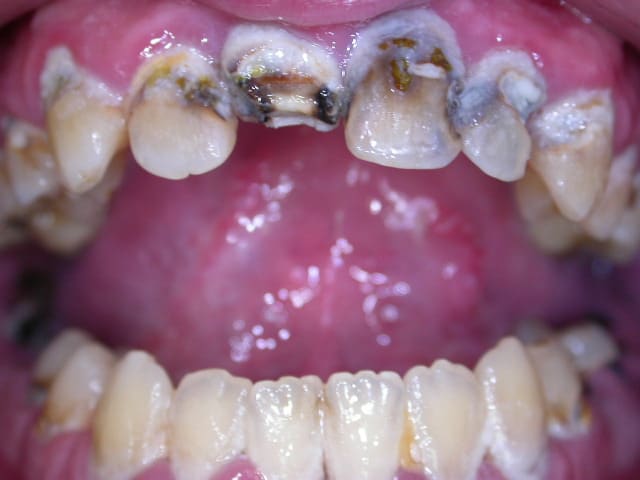

recommandé par une patiente... son amie...

la bridge "amovible"... "réparé au centre médical"...

motif de la consultation: "une infection de la dent du fond" commencée à traiter par 1 clamoxyl, en automédication...